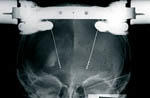

Die Operation erfolgt in zwei Schritten: Zunächst werden beide Elektroden in örtlicher Betäubung implantiert. Dazu wird ein Metallring auf dem Kopf fest angebracht. Mit diesem Stereotaxiering werden spezielle Computertomogramme und Röntgenaufnahmen angefertigt, mit deren Hilfe die Koordinaten der Zielpunkte in den Basalganglien berechnet werden. Die Elektrode wird schmerzfrei und zielgesteuert (stereotaktisch) in die zuvor definierten Hirnzentren eingeführt. Auch während der Operation wird die Lage der Elektroden mit Röntgenaufnahmen regelmäßig kontrolliert.

Über Mikroelektroden werden aus den Zielgebieten zusätzlich Entladungen der Nervenzellen abgeleitet, die spezifisch für jede Zellgruppe sind und daher eine zusätzliche Sicherheit bei der Lagebestimmung der Elektroden in den nur wenige Millimeter messenden Strukturen bieten. Probestimulationen geben letztlich die entscheidende Information darüber, ob die nur anvisierten Zielpunkte erreicht wurden und die Symptome des Patienten unterdrückt werden können.